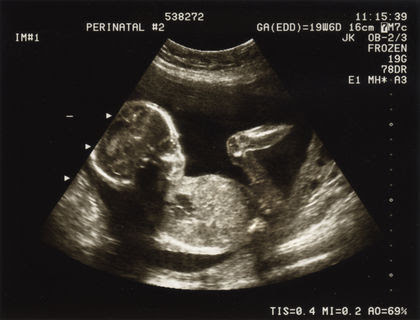

Prenatal care is essential for ensuring the health and well-being of both the mother and the baby throughout pregnancy. It includes regular check-ups, tests, and counseling to monitor fetal growth and manage potential risks.

Importance: Regular prenatal visits help detect any issues early and ensure that both mother and baby stay healthy throughout pregnancy.